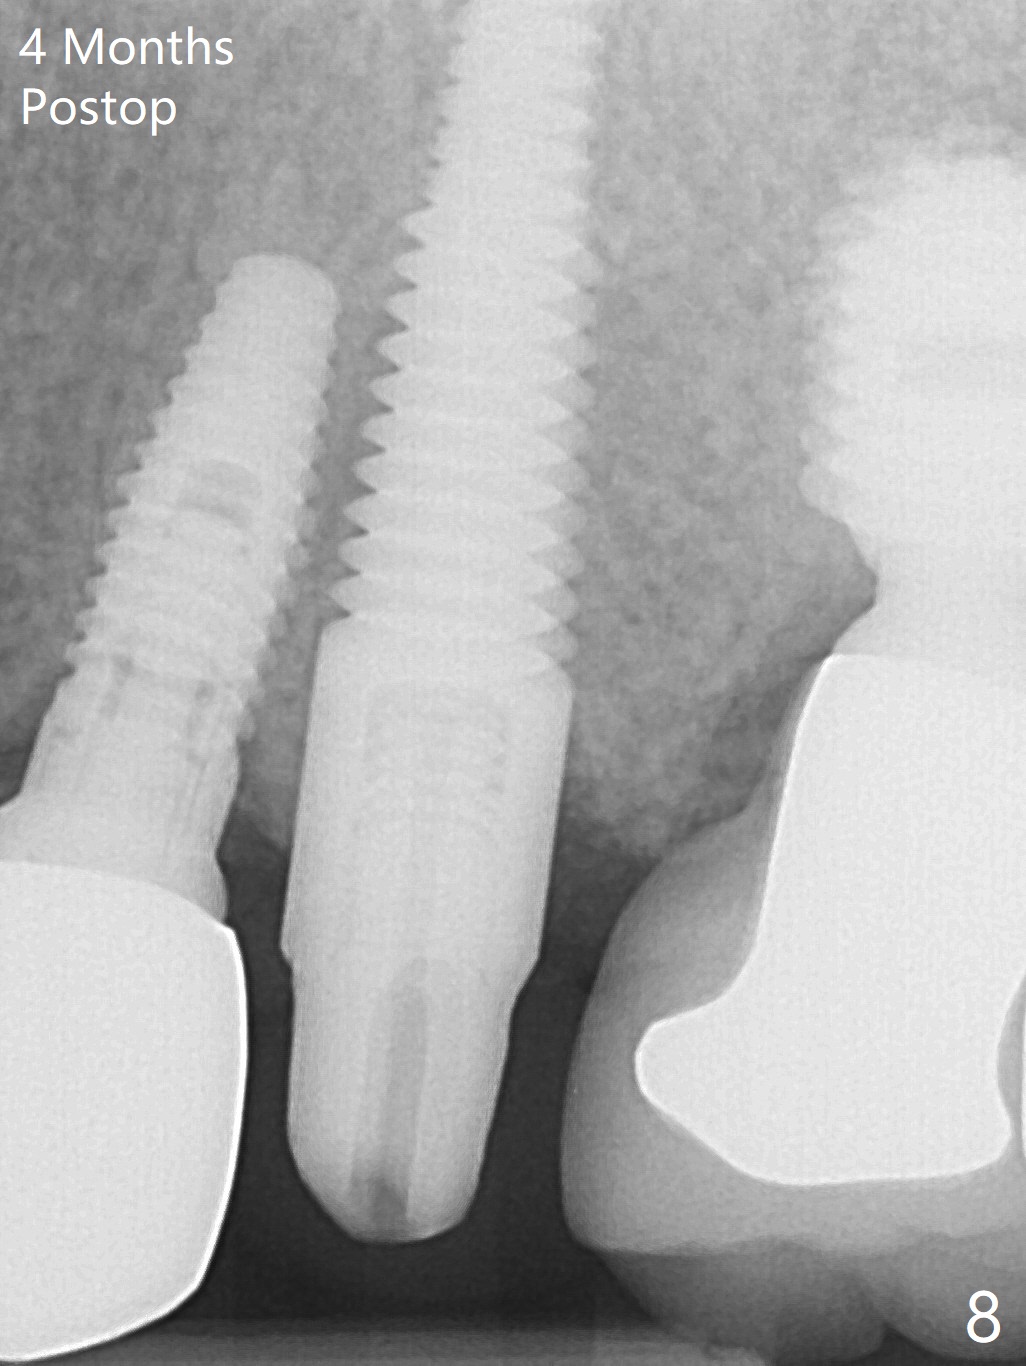

When the tooth #13 with buccal fistula is extracted, the root is found to have vertical fracture (Fig.1). The socket is 14 mm deep (gingival level); the initial osteotomy depth is 20 mm (6 mm to be in the native bone for primary stability, Fig.2). A 4.5x20 mm tissue-level implant (>60 Ncm) is going to be placed in the palatal aspect of the oval socket (Fig.3-5). The localized defect in the buccal plate as indicated by labels (* (Vanilla/Osteogen), B (buccal) and < (perforation) in Fig.6,7 (CBCT coronal and axial sections) is repaired by the bone graft. The bone and gingiva are healthy around the implant nearly 4 months postop (Fig.8,9).